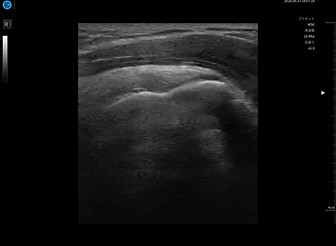

痛みをエコー評価で「見える化」

運動器疾患に多い筋肉や筋膜・腱・靭帯・神経などの状態はレントゲン検査では分かりません。当院では、エコー評価を行うことで、痛みを「見える化」。正確に身体の状態を把握し、納得して施術を受けていただけます。また、修復過程も確認できるためより早期改善・早期復帰に期待ができます。

02 レントゲンでは見えない筋・腱・靭帯・神経を「見える化」

スポーツ障害のうち、筋・腱・靭帯などの損傷の割合は全体の80~90%以上を占める、とも言われています。これら軟部組織の損傷を見える化できるのがエコー評価です。